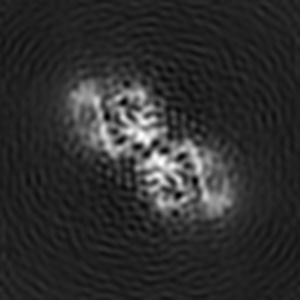

Helical reconstruction

3.9 Å

Cryo-EM structure of human islet amyloid polypeptide (hIAPP, or amylin) fibrils seeded by patient extracted fibrils, polymorph 2